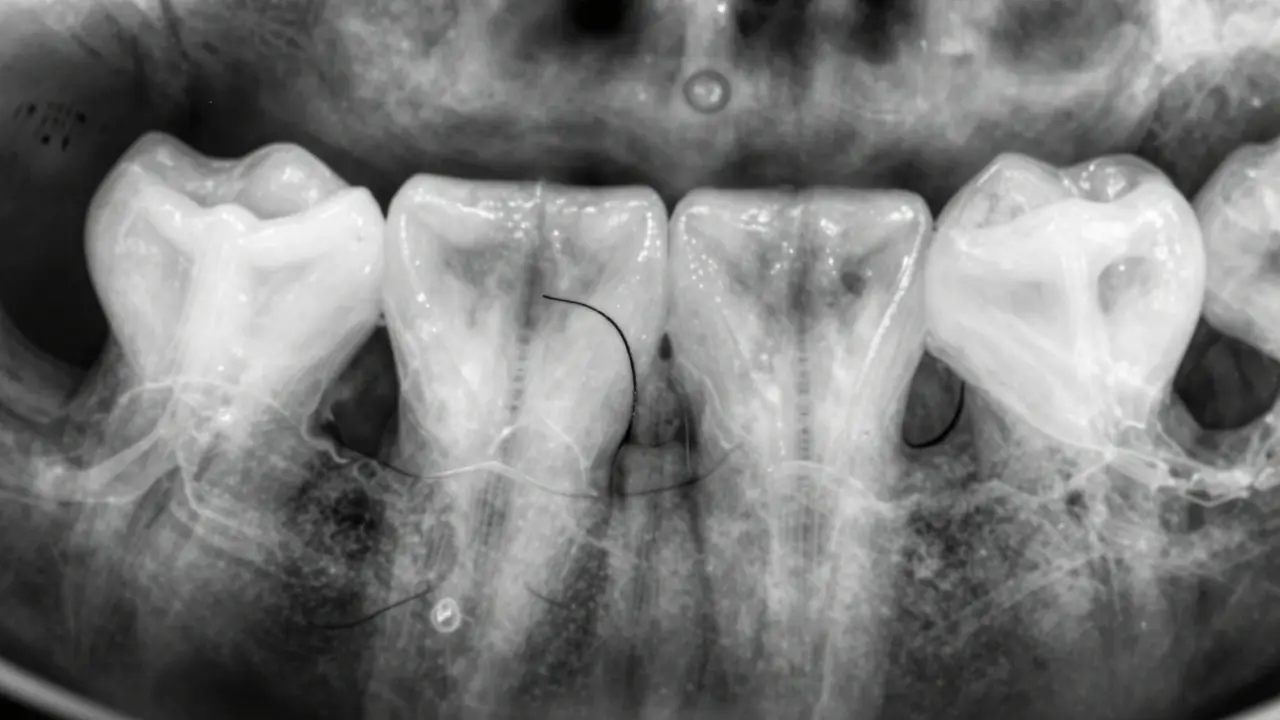

Zuby na rentgenu vypadají jako světlé obrazce, protože jsou složeny z hustého minerálu - hydroxyapatitu. Tento materiál blokuje rentgenové paprsky, takže na snímku zůstávají bílé nebo šedé. Čím hustší je tkáň, tím světlejší je její obraz. Když se zubní kaz začne rozvíjet, mineralizovaná struktura zubu se rozpadá. Místo, kde došlo ke ztrátě minerálů, propouští více paprsků - a na snímku to vypadá jako tmavší skvrna.

Tato tmavá oblast není vždy černá. Často je jen o něco tmavší než okolní zub. Pokud je karies malý a na začátku, může být vidět jen jako tenká čára mezi dvěma zuby - právě tam, kde se často ukládá plak a kde čistění zubním kartáčkem nestačí. To je ten tzv. mezizubní kaz, který je nejčastější formou karies u dospělých.

Mezizubní karies začíná pod povrchem zubu, kde se neobjeví žádná viditelná díra. Oči zubaře nebo vás samotného to nezjistí. Dokonce i zubní nitě mohou jen podezřívat, že je tam něco špatně. Až rentgen odhalí, že se mineralizace zubu v místě kontaktu mezi zuby zmenšila - a to je první známka karies.

Na rentgenovém snímku se mezizubní karies projevuje jako široká nebo úzká tmavá linie, která se táhne od povrchu zubu směrem do jeho nitra. Pokud je ještě jen v emalové vrstvě, zubří zubař může doporučit jen lepší hygienu a fluoridovou péči. Pokud už sahá do dentinu, je třeba vyplnit. A pokud se blíží k zubnímu nervu, může být potřeba kořenová léčba.